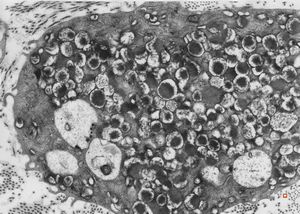

M,40y. | granular cell tumor

F,30y. | granular cell tumor